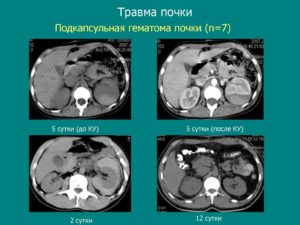

Гематома почки